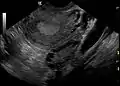

The syndrome acquired its most widely used name due to the common sign on ultrasound examination of multiple (poly) ovarian cysts. These "cysts" are actually immature follicles not cysts. The follicles have developed from primordial follicles, but the development has stopped ("arrested") at an early antral stage due to the disturbed ovarian function. The follicles may be oriented along the ovarian periphery, appearing as a 'string of pearls' on ultrasound examination.

Not everyone with PCOS has polycystic ovaries (PCO), nor does everyone with ovarian cysts have PCOS; although a pelvic ultrasound is a major diagnostic tool, it is not the only one.[56] The diagnosis is straightforward using the Rotterdam criteria, even when the syndrome is associated with a wide range of symptoms.

Transvaginal ultrasound scan of polycystic ovary

Polycystic ovary as seen on sonography

- Gynecologic ultrasonography, specifically looking for small ovarian follicles. These are believed to be the result of disturbed ovarian function with failed ovulation, reflected by the infrequent or absent menstruation that is typical of the condition. In a normal menstrual cycle, one egg is released from a dominant follicle – in essence, a cyst that bursts to release the egg. After ovulation, the follicle remnant is transformed into a progesterone-producing corpus luteum, which shrinks and disappears after approximately 12–14 days. In PCOS, there is a so-called "follicular arrest"; i.e., several follicles develop to a size of 5–7 mm, but not further. No single follicle reaches the preovulatory size (16 mm or more). According to the Rotterdam criteria, which are widely used for diagnosis,[10] 12 or more small follicles should be seen in an ovary on ultrasound examination.[57] More recent research suggests that there should be at least 25 follicles in an ovary to designate it as having polycystic ovarian morphology (PCOM) in women aged 18–35 years.[63] The follicles may be oriented in the periphery, giving the appearance of a 'string of pearls'.[64] If a high resolution transvaginal ultrasonography machine is not available, an ovarian volume of at least 10 ml is regarded as an acceptable definition of having polycystic ovarian morphology instead of follicle count.[63]

Ultrasound findings in PCOS include enlarged ovaries with peripheral follicles in a "string of pearls" configuration.